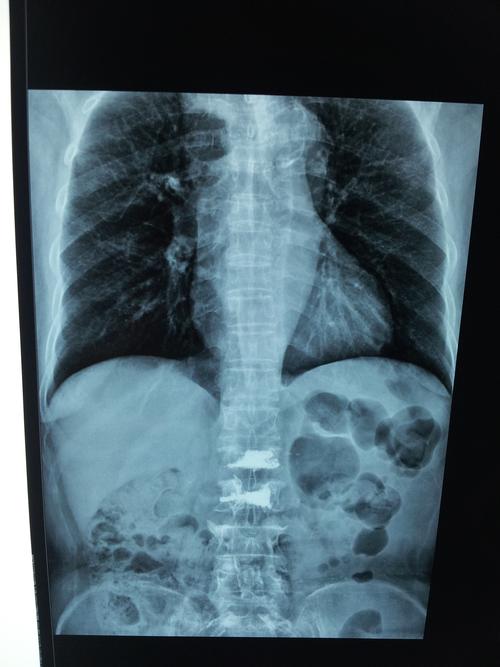

胸片及ct观察picc管